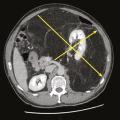

Radiothérapie dans le traitement des sarcomes

Depuis les années 1980, la chirurgie conservatrice suivie d’une radiothérapie postopératoire est devenue le standard thérapeutique pour la plupart des sarcomes des tissus mous des membres.1,2 Le bénéfice de l’association radio-chirurgicale est surtout observé chez des patients avec des tumeurs de haut grade, de localisation profonde…